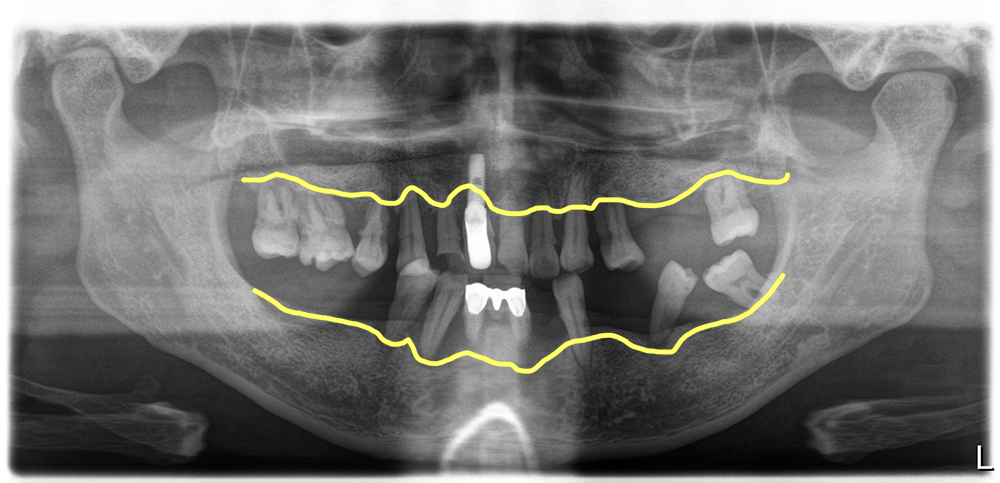

어제 치료를 마무리한 환자 사례인데요. 평소 치솔질이 제대로 되지 않고 구강위생관리가 전혀 되지 않아서 결국 잇몸질환으로 잇몸뼈인 치조골이 모두 무너져 내려 모든 치아를 뽑고 전체임플란트를 하게 된 이야기를 좀 해 드리겠습니다.

영상에서 보시는 것처럼 치료전 치아상태가 아주 좋지 않습니다. 치조골이 모두 녹아서 치아들이 많이 흔들릴뿐 아니라 치석과 프라그가 치아에 잔뜩 붙어있습니다. 이런 상태를 보았을 때 우리는 전체임플란트 치료후 위생관리를 더 신경쓰게 해야 한다는 것을 생각하게 됩니다.

이 환자분은 40대의 젊은 남성이었는데 아무래도 치아가 하나둘 망가지면서 관리를 포기한 상태였던 거 같습니다. 입 안에 임플란트가 앞니에 하나 있었는데 해당 임플란트는보기에 흉하게 만들어져 있을 뿐 아니라 이미 임플란트주위염이 생겨져 있어서 해당 임플란트도 다른 치아처럼 제거를 하기로 했습니다.

염증조직을 모두 제거후 위아래 임플란트 21개 식립(위 11개, 아래 10개)

염증이 심한 치아들과 임플란트를 모두 제거한 후 염증조직들을 깨끗이 제거해 줍니다. 염증조직을 충분히 제거하지 않고 남겨두면 해당 조직때문에 식립해 놓은 임플란트에 감염이 올 수 있기 때문에 깨끗한 염증제거는 필수입니다.